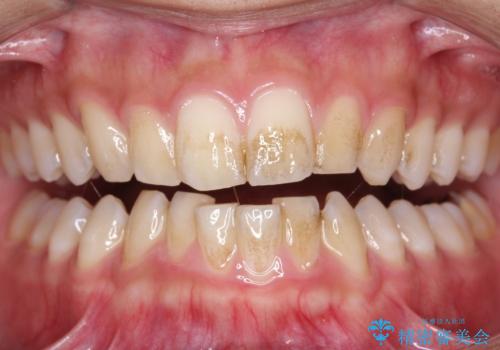

矯正治療中も歯の黄ばみをきれいにしたい

担当医 歯科衛生士